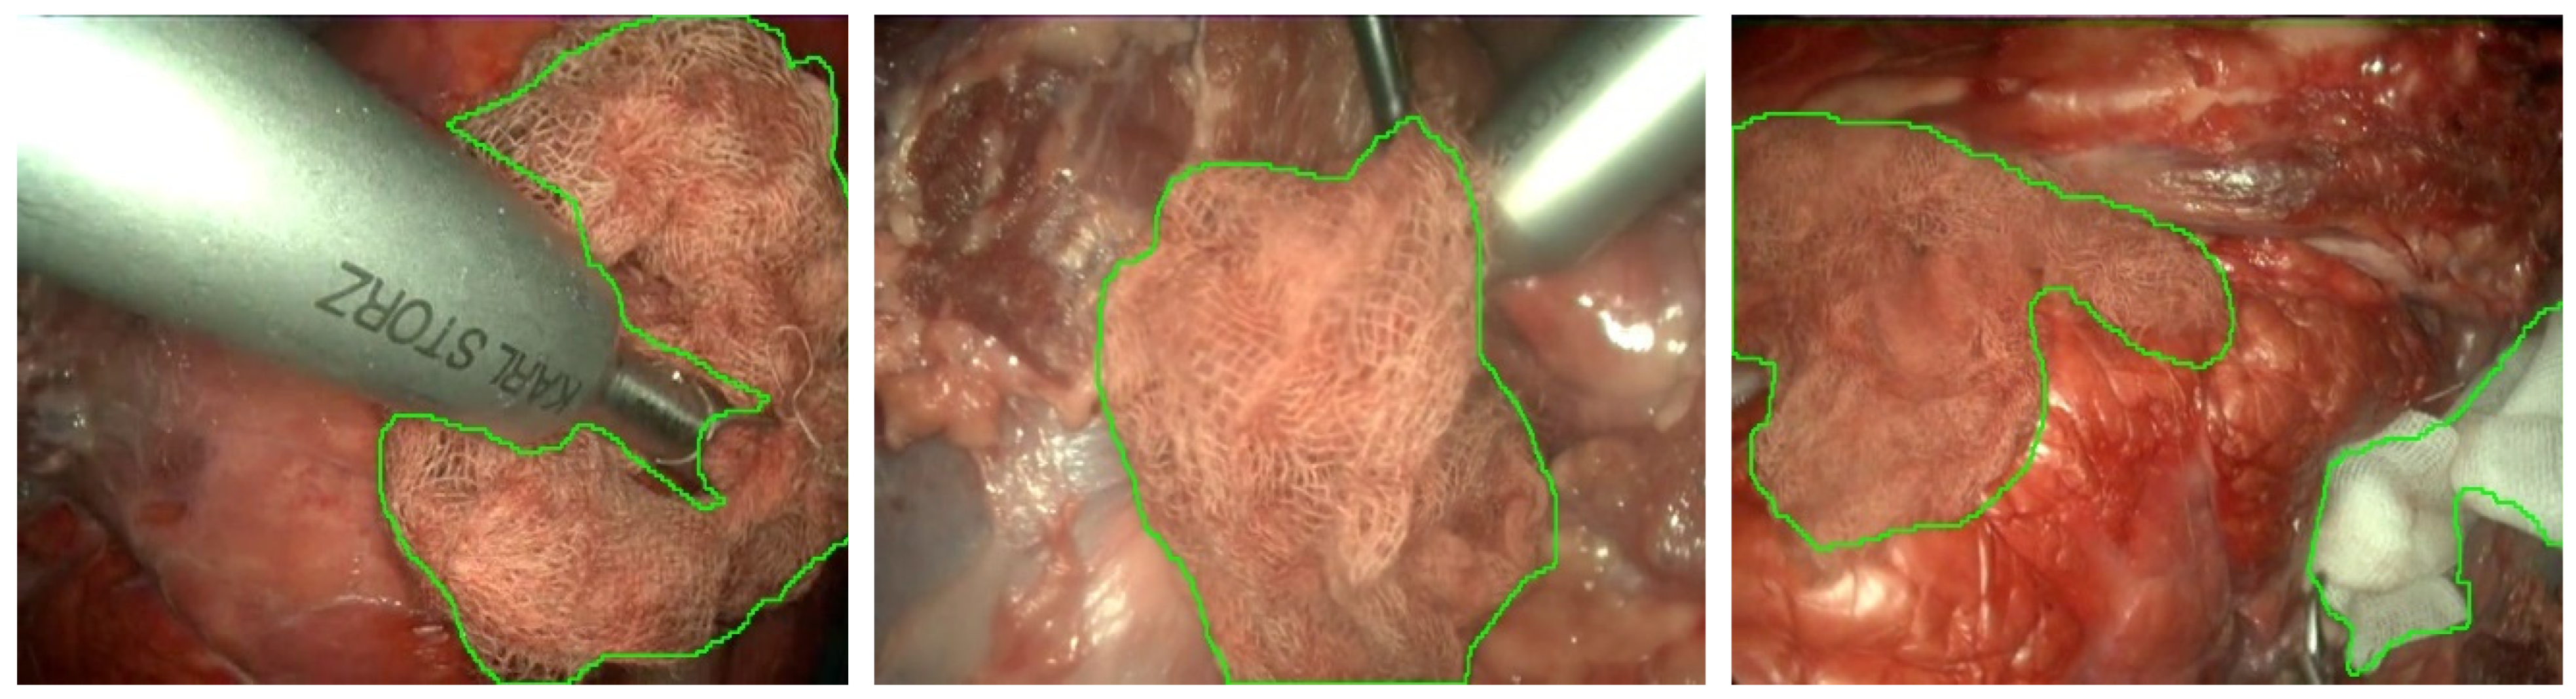

2.1. Dataset

2.4. Gauze Coarse Segmentation

2.5. Gauze Segmentation